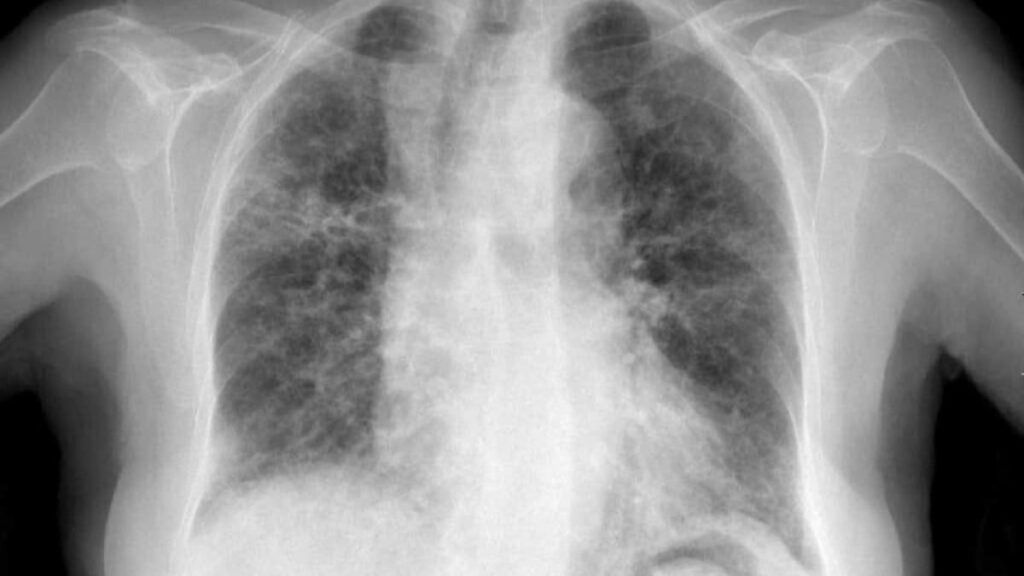

Hemorragia alveolar difusa

Definición y patogénesis La Hemorragia Alveolar Difusa (HAD) es un síndrome clínico que se manifiesta generalmente con hemoptisis, anemia y...